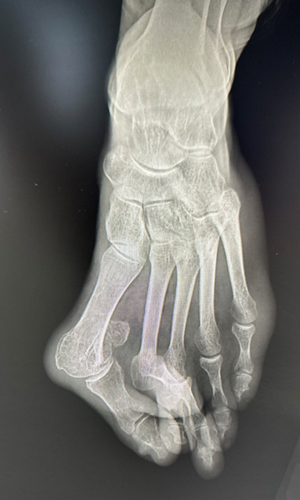

TOTAL ANKLE REPLACEMENT :: ORIF CALCANEUS :: ORIF ANKLE FRACTURE DISLOCATION :: COMPLEX BUNION AND LESSER TOE CORRECTION :: TALUS FRACTURE -1 :: TALUS FRACTURE -2 :: LISFRANC REPAIR :: COMPLEX TRIPLE ARTHRODESIS 1 :: COMPLEX TRIPLE ARTHRODESIS 2 :: MINIMALLY INVASIVE BUNION REPAIR 1 :: MINIMALLY INVASIVE BUNION REPAIR 2 :: ARTHROSCOPIC CARTILAGE REPAIR :: TENEX SPUR DEBRIDEMENT :: Haglunds Debridement and Achilles Repair